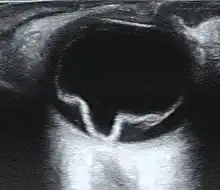

| Ultrasound of a retinal detachment in a patient presenting with complete vision loss and light perception only. | |

Ultrasound, MRI, and CT scan are commonly used to diagnose retinal detachment.